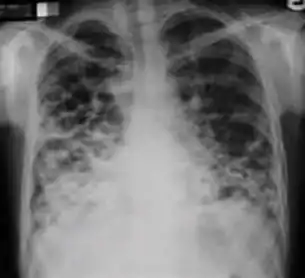

Chest x-ray showing patchy opacification on the upper right and mid-zone lung with fibrotic shadows, as well as bilateral hilar lymphadenopathy.